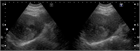

1. また、典型症例について画像を用いて解説した。詳細は本文を参照されたい。

1. ウイルス性肝硬変にて定期画像診断(サーベイランス)中に発見された肝細胞癌で、ガイドラインの治療アルゴリズムに沿って肝切除にて治療した症例である。